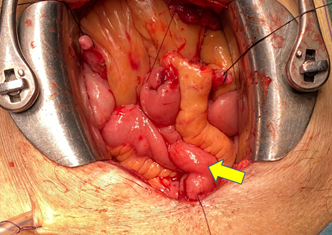

Sau gần 4 giờ phẫu thuật, khối u cùng toàn bộ bàng quang của người bệnh đã được cắt bỏ, bàng quang mới được tạo hình từ một đoạn hồi tràng. Hiện tại sau 4 ngày hậu phẫu, sức khỏe người bệnh ổn định.

Hình ảnh bàng quang tân tạo